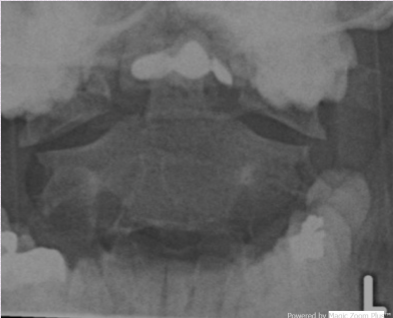

What type of radiograph and view is this?

Open Mouth Radiograph of (C1/C2)

What is this radiograph revealing?

Jefferson Burst Fracture (C1)

Open mouth radiograph